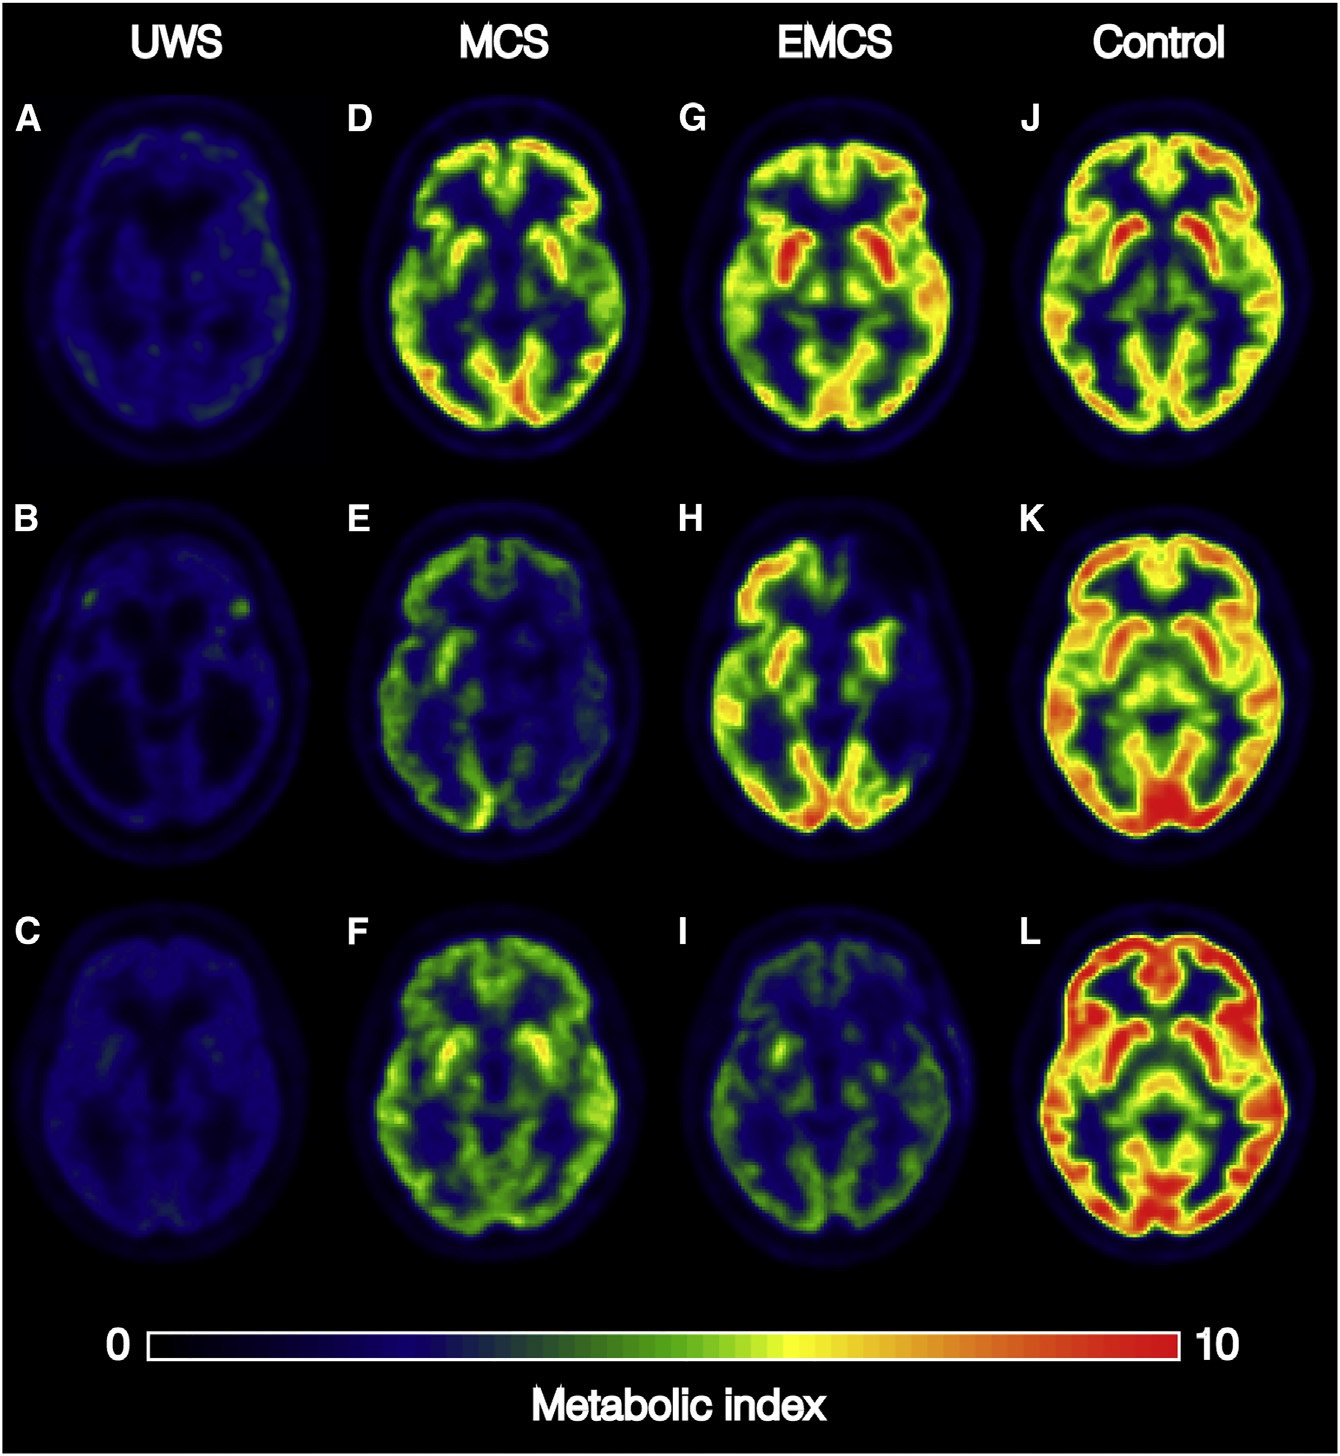

Состояние сознания хорошо диагностируется обычной позитронно-эмиссионной томографией с применением 18F-фтордезоксиглюкозы (PET-FDG). Диагностика показывает уровень метаболизма глюкозы в клетках

Исследование показало, что мозговой метаболизм хорошо коррелирует с уровнем сознания у пациентов.

Восстановление сознания спустя год у пациентов с разным уровнем метаболизма: в вегатативном состоянии (UWS) и с минимальным сознанием (MCS, EMCS)

Был определён энергетический уровень метаболизма (42% от нормального), который является критическим. Практически ни один пациент с метаболизмом ниже этого уровня не пришёл в сознание в течение года после обследования. С другой стороны, 94% пациентов с метаболизмом выше этого энергетического уровня проявляли признаки сознания при обследовании или начали реагировать на раздражители в течение года после получения травмы.